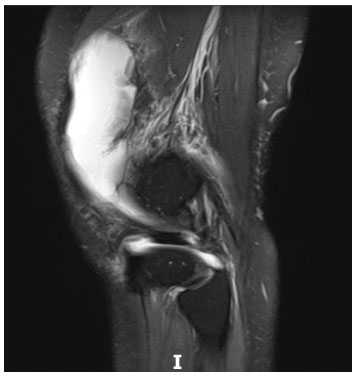

Foi submetida a exames laboratoriais, radiografia do joelho direito e ressonância nuclear magnética (RNM) no joelho e ombro direito. A radiografia apontou apagamento do coxim gorduroso suprapatelar, sugerindo reação sinovial (Figura 1). A RNM do joelho apontou acentuado derrame articular, pelo que, foi realizada punção do líquido articular (Figura 2). A análise do líquido apresentou 2.240 leucócitos por mm3, com 1.366 polimorfonucleares por mm3. As culturas e a bacterioscopia foram negativas. A RNM do ombro apontou derrame articular acromioclavicular e glenoumeral.